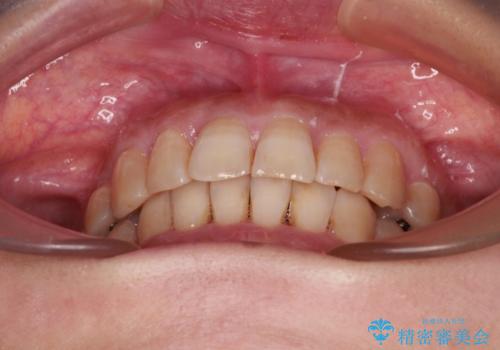

ディープバイトと前歯のデコボコ インビザラインによる矯正治療

下顎大臼歯が手前に倒れていたため、起き上がらせることで咬み合わせ高さを挙上し、ディープバイトと叢生を改善することとしました。

インビザライン特有の奥歯の噛みにくさが治療後半に発言しましたが、無事に終了させることができました。